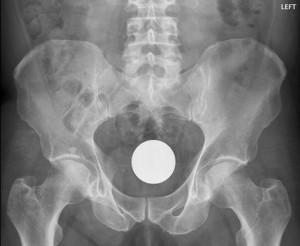

ბილიარდის ბურთი

10 (1)